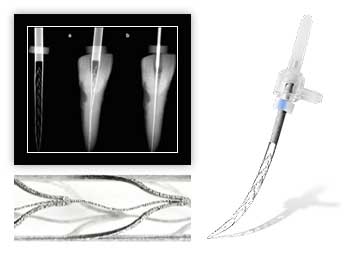

Наше оборудование